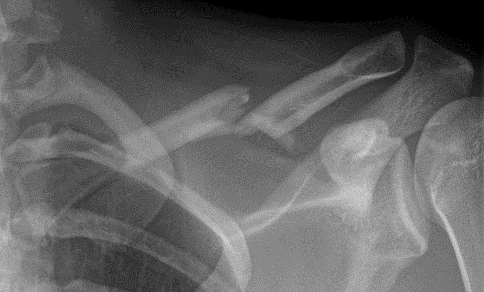

U bent onder behandeling bij Amsterdam UMC omdat u uw sleutelbeen heeft gebroken. Afhankelijk van het soort breuk van uw sleutelbeen, heeft uw traumachirurg in overleg met u besloten de breuk met of zonder operatie te behandelen. In deze folder krijgt u informatie over de behandeling en het herstel na een gebroken sleutelbeen, met of zonder operatie.